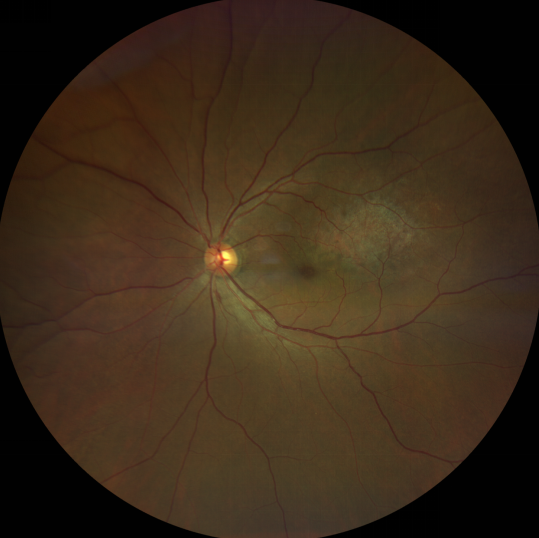

脈絡(luò)膜黑色素瘤是成年人常見的眼內(nèi)惡性腫瘤,其患病率在我國居眼內(nèi)惡性腫瘤的第二位,僅次于視網(wǎng)膜母細(xì)胞瘤。其惡性程度高,不僅可致患者喪失視力,而且嚴(yán)重威脅患者生命,即使在沒有明確轉(zhuǎn)移前摘除患眼眼球,其5年死亡率也有17%-53%。

脈絡(luò)膜黑色素瘤是葡萄膜惡性腫瘤中較多的一種。葡萄膜腫瘤主要發(fā)生于脈絡(luò)膜、睫狀體和虹膜。其中,脈絡(luò)膜腫瘤占80%,睫狀體腫瘤占12%,虹膜腫瘤占8%。惡性程度高的腫瘤主要發(fā)生于脈絡(luò)膜。發(fā)生于睫狀體的腫瘤惡性程度偏低,發(fā)生于虹膜的腫瘤多數(shù)為良性。脈絡(luò)膜黑色素瘤的特點(diǎn)是惡性程度高、易侵襲轉(zhuǎn)移、預(yù)后極差,嚴(yán)重威脅患者的視力和生命。其發(fā)病率有種族差異性,以高加索及白種人居多,黑人發(fā)病率低,亞洲人居于中間。

脈絡(luò)膜黑色素瘤患者在發(fā)病早期無眼痛等癥狀,當(dāng)腫瘤較小時(shí)較難發(fā)現(xiàn),隨著病程進(jìn)展,腫瘤增大,發(fā)生滲出性視網(wǎng)膜脫離或累及黃斑,視力下降才就診。

脈絡(luò)膜黑色素瘤惡性程度高,50%的患者會發(fā)生轉(zhuǎn)移,轉(zhuǎn)移到肝、肺等遠(yuǎn)處臟器,常見的轉(zhuǎn)移方式是經(jīng)鞏膜導(dǎo)管擴(kuò)散,經(jīng)視神經(jīng)蔓延者罕見。一旦發(fā)生轉(zhuǎn)移,1年生存率只有10%,即絕大多數(shù)病人在半年至1年間會失去生命。因此,早期診斷和選擇合適的治療方式對有效提高局部腫瘤的控制率、降低腫瘤的遠(yuǎn)處轉(zhuǎn)移率、延長患者的生存率具有重要意義。